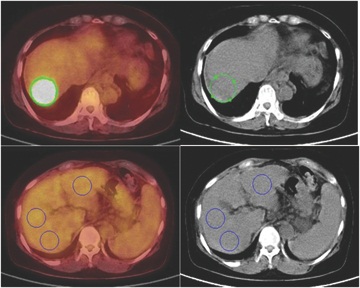

(18)F-Fluorodeoxyglucose positron-emission tomography ((18)F-FDG PET) has been used to assess the biological behavior of hepatocellular carcinoma (HCC). In this study, we investigated the usefulness of (18)F-FDG PET for predicting tumor progression and survival in patients with intermediate Barcelona Clinic Liver Cancer (BCLC) intermediate-stage HCC treated by transarterial chemoembolization (TACE).

From February 2006 to March 2013, 210 patients treated with TACE, including 77 patients with BCLC intermediate-stage HCC, underwent examination by (18)F-FDG PET. (18)F-FDG uptake was calculated based on the tumor maximum (Tmax) standardized uptake value (SUV), the liver mean (Lmean) SUV, and the ratio of the Tmax SUV to the Lmean SUV (Tmax/Lmean).

(18)F-FDG uptake calculated by the Tmax/Lmean using PET predicted tumor progression and survival in patients with BCLC intermediate-stage HCC treated by TACE.

- 18F-FDG PET은 두경부암, 폐암, 췌장암, 대장암 그리고 전이성 간암 등에 유용한 진단적 도구로 사용되었으나 간암에서는 아직 유용성에 대해 논란이 있습니다. sorafenib 으로 치료한 간암환자에서의 독립적인 예후 인자를 찾아내기 위한 PET 연구가 진행되는 등 간암환자에서의 PET 시행에 대한 연구가 활발히 진행되고 있습니다. 간암을 바르셀로나 임상병기 (BCLC) 로 분류하였을 때 중간병기의 간암의 치료로 화학색전술이 권고되는데 치료받은 환자의 장기 생존률은 만족스럽지 못하여 그 치료반응의 평가와 모니터링이 중요한 실정입니다. 본 논문에서는 순천향 대학병원에서 치료받은 총 77명의 중간병기 간암 환자를 대상으로 진단 당시의 PET 의 평균 SUV(T max/L mean) 가 화학색전술 치료후의 장기 생존률과 종양진행을 예측하는 인자로 유용하게 사용 될 수 있음을 확인하였고 앞으로 간암환자에서의 PET 연구가 더 활발히 진행 될 수 있는 단초가 될 수 있을 것이라 생각됩니다.